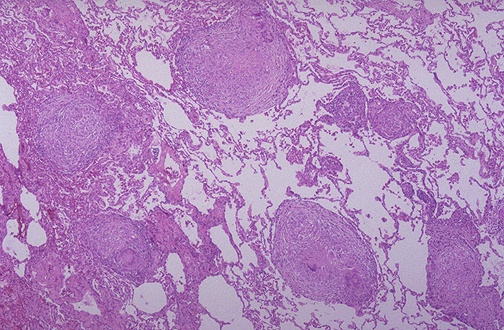

Image 11.2

The low power microscopic appearance of the lung is shown here.